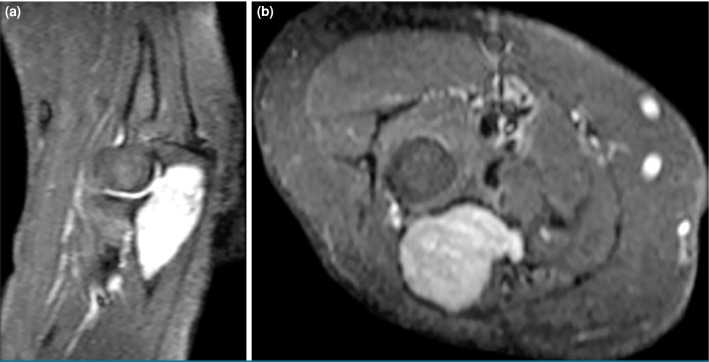

骨内神经鞘瘤是一种极为罕见的良性肿瘤,起源于周围神经系统的雪旺细胞。虽然这些肿瘤常见于下颌骨和骶骨,但它们发生在长骨,特别是尺骨,是罕见的。59岁女性患者因右肘疼痛和肿胀两年入院。x线影像学显示尺骨近端干骺端皮质扩张和变薄的溶解性病变,而磁共振成像显示不规则边界病变通过皮质侵蚀延伸到关节。鉴别诊断包括单纯性骨囊肿、内生纤维瘤、巨细胞瘤和转移。手术包括刮除和植骨,病理诊断为骨内神经鞘瘤。免疫组化染色显示SOX10和S100阳性表达,证实诊断。术后恢复顺利,患者在6个月的随访中恢复了全活动能力,无疼痛。总之,这个病例强调了在良性骨病变鉴别诊断中考虑骨内神经鞘瘤的重要性,特别是在罕见的部位,如尺骨。组织病理学检查仍然是准确诊断的必要条件。

Intraosseous schwannomas are extremely rare benign tumors originating from Schwann cells of the peripheral nervous system. While these tumors are commonly found in the mandible and sacrum, their occurrence in long bones, particularly the ulna, is uncommon. A 59-year-old female patient was admitted with a two-year history of pain and swelling in her right elbow. Radiographic imaging revealed a lytic lesion with cortical expansion and thinning in the proximal ulna metaphysis, while magnetic resonance imaging showed a lesion with irregular borders extending into the joint via cortical erosion. Differential diagnoses included a simple bone cyst, enchondroma, giant cell tumor, and metastasis. Surgical procedure involved curettage and bone grafting, and the lesion was diagnosed histologically as an intraosseous schwannoma. Immunohistochemical staining showed positive expression of SOX10 and S100, confirming the diagnosis. Postoperative recovery was uneventful, and the patient regained a full range of motion without pain at her six-month follow-up. In conclusion, this case underscores the importance of considering intraosseous schwannoma in the differential diagnosis of benign bone lesions, particularly in rare locations such as the ulna. Histopathological examination remains essential for an accurate diagnosis.